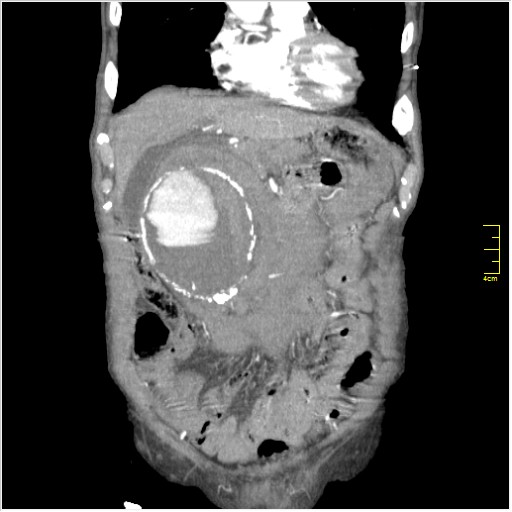

Пациент Т. 64 года, обратился на КТ брюшной полости амбулаторно (!), по направлению семейного врача с диагнозом abdominal mass, буквально: образование брюшной полости.

Huge abdominal aorta aneurism. Simple renal cortical cysts (Bosniak type 1).